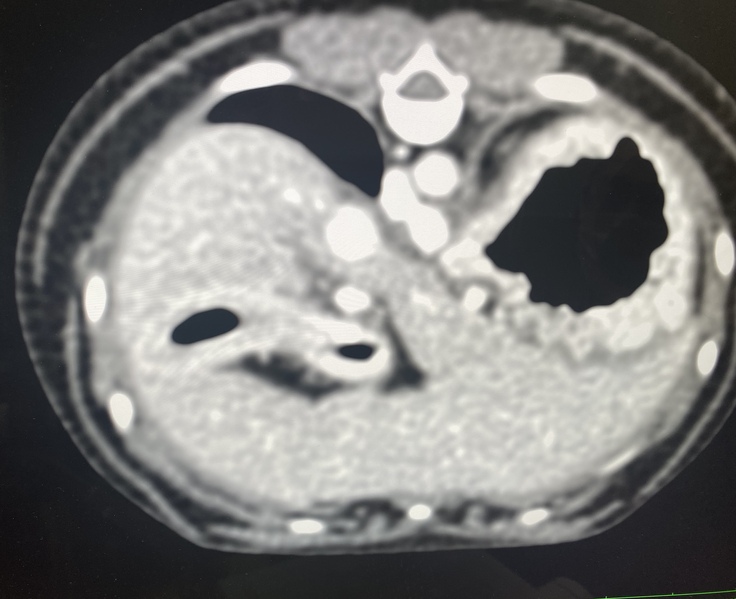

↓この診察内容で門脈体循環シャントを

先生が発見して下さいました。

○↑に載せてある診療明細書の腹部超音波エコー・x線検査の結果

↓CTの結果です

○↑に載せてある全身麻酔によるCT検査CTで2本の太いシャント血管があった事

シェリーの場合はシャント血管2本見つかりました。手術1回の可能性50%2回以上の可能性50%との事でした。